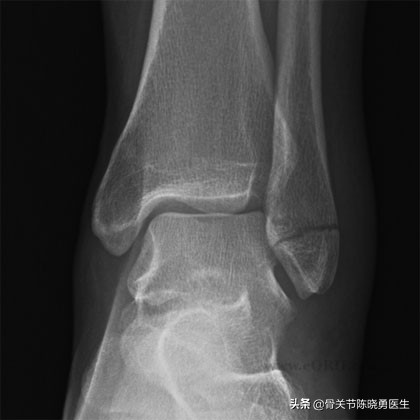

踝关节损伤

由于踝关节在解剖结构上和腓骨的紧密联系,踝关节损伤时不应忽视腓骨受伤的可能。

腓骨骨折最常见的位置就在踝关节水平。如有不伴有踝关节其他结构的损伤,发生于踝关节水平的腓骨骨折,又被称为单纯腓骨骨折。这种损伤往往发生于踝关节旋转扭曲的时候,踝关节内侧的韧带和骨骼均保持完好。此时踝关节的稳定性不会受到影响,通常可以采用简单的保护治疗即可。

在这种情况下,使用石膏托或支具就可以对踝关节起到很好的支撑作用。拐杖要使用数周的时间,以利于肿胀和疼痛的消退。疼痛减轻后,患者就可以开始康复锻炼,并逐渐恢复行走。

有时,腓骨骨折会合并踝关节内侧骨骼(又称为内踝)或韧带(称为三角韧带)的损伤,通常就需要更积极的治疗。在这种情况下,医生又称之为“双踝骨折”,必须要通过手术来恢复踝关节的稳定性。如果不进行手术,则踝关节的对位会逐渐发生异常,从而导致踝关节炎的发生。

腓骨骨折可能导致的另一种损伤就是下胫腓联合损伤。下胫腓联合包含了数根韧带,它刚好在踝关节的上方,把胫骨和腓骨紧紧地连在一起。 当下胫腓联合在踝关节受到损伤时,通常需要通过手术来恢复骨骼的正确位置。